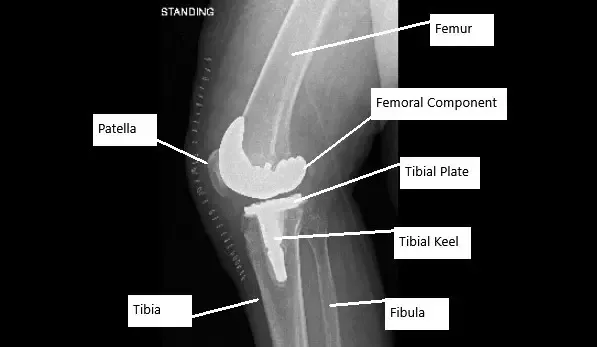

Radiografía que muestra una cirugía de reemplazo total de rodilla en un paciente con AVN de rodilla.

- Reemplazo total de rodilla: En casos graves, cuando la articulación está gravemente dañada, puede ser necesaria una cirugía de reemplazo de rodilla. Este procedimiento consiste en retirar el hueso y el cartílago dañados y sustituirlos por componentes artificiales.